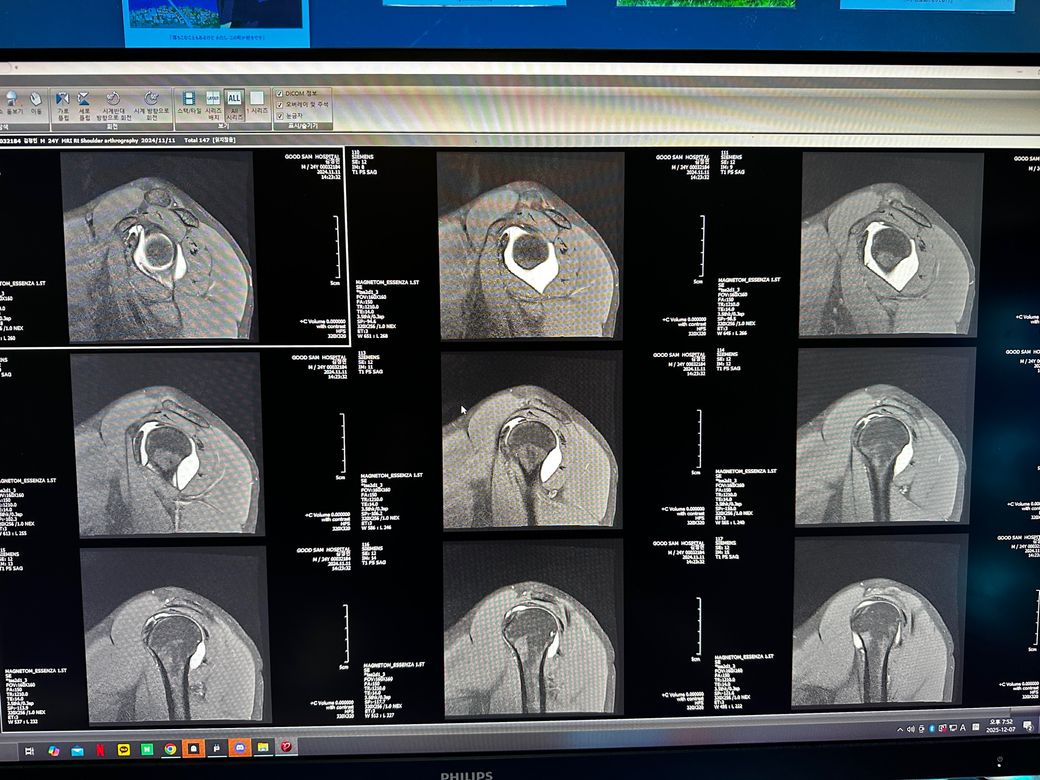

오른쪽어깨 관절mri좀 봐주세요 사진첨부입니다

오룬쪽어깨관절 엠알아이 결과좀 봐주세요

오른쪽어깨관절부분입니다

관절입니다

• 1번 째 사진

• 2번 째 사진

• 3번 째 사진

조영제가 들어간 것으로 보이며, "회전근개(특히 극상근) 파열이나 큰 손상은 뚜렷하게 보이지 않는 편"입니다.

관절와순(Labrum) 주변에 조영제가 퍼져 보이지만, "명확한 파열 소견은 사진만으로 단정 어렵고 경미한 손상.염증 가능성"은 있습니다.

관절 안쪽에 "약한 염증/활액 증가"는 있어 보이며, 충돌증후군 초기 형태 가능성이 있습니다.